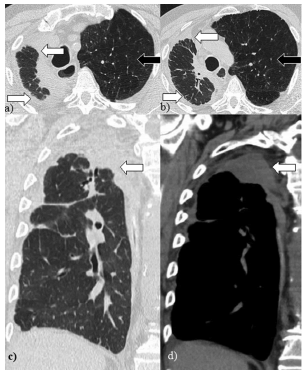

El SRE presenta algunas características imagenológicas similares a las enfermedades intersticiales con franca afectación de los lóbulos superiores (aunque en menor medida pueden afectarse otros lóbulos). Se identifican opacidades en vidrio esmerilado e intersticiales que evolucionan con engrosamientos de los septos interlobulillares, bronquiectasias-bronquiolectasias por tracción y panalización con alteración arquitectural asociado a pérdida de volumen del parenquima pulmonar3-5. Figura 2